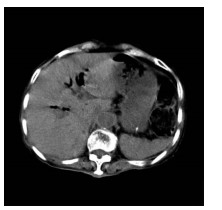

肝病超声诊断指南

中华医学会超声医学分会, 中国研究型医院学会肿瘤介入专业委员会, 国家卫生和健康委员会能力建设和继续教育中心超声医学专家委员会

2021, 37(8): 1770-1785. DOI: 10.3969/j.issn.1001-5256.2021.08.007

摘要(3138) HTML (6640) PDF (9311KB)(810)

超声检查无创、实时、价廉,无辐射、便于反复进行,是最常用的肝脏影像学检查方法。近年来,超声检查新技术如超声造影、弹性成像发展迅速,可有效鉴别肝内占位性病变性质、评估肝纤维化和门静脉高压程度以及监测肝病治疗效果,在临床肝病及其介入治疗中发挥重要诊断价值。本指南规范了肝病多模态超声技术(灰阶超声、彩色多普勒超声、超声造影、弹性超声)检查的仪器调置、患者准备及医生检查方法;对肝脏弥漫性病变(炎性病变、纤维化、硬化)、多种占位性病变及肝病介入操作的多模态超声技术诊断标准进行了定义和规范,同时推荐了超声监测周期及肝脏疾病超声诊断报告书写规范。